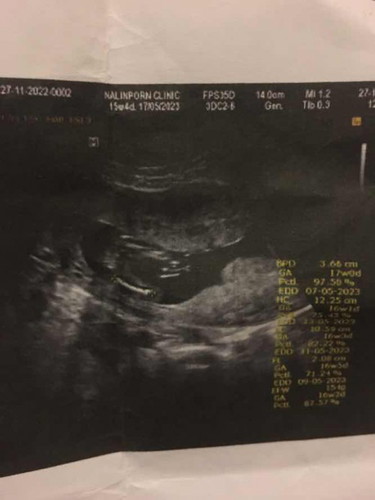

แม่ๆช่วยดูหน่อยค่ะว่าน้องเป็น ผญ หรือ ผช

ตรงหว่างขามองไม่ชัดเลยค่ะแม่รออายุครรภ์เยอะกว่านี้แล้วซาวใหม่นะคะ